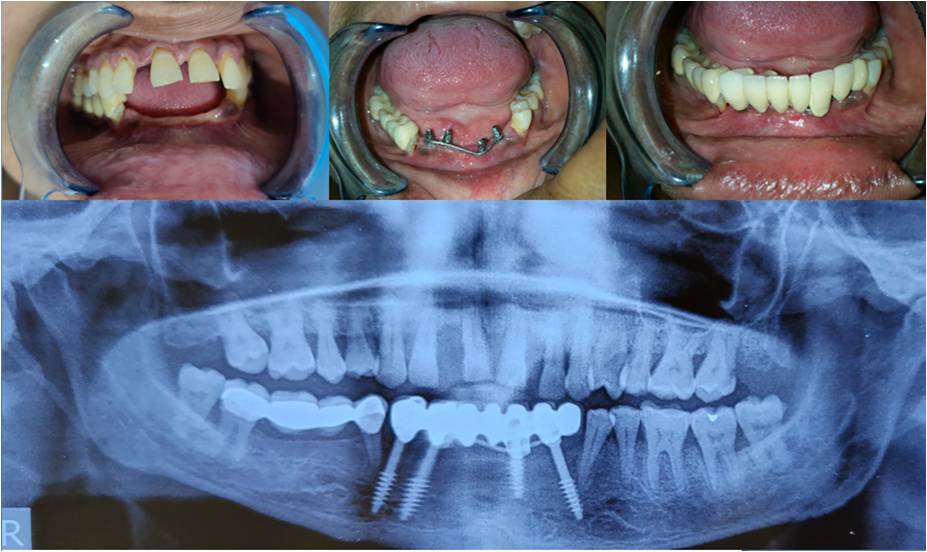

We are a team of 3 certified dentists specialised in offering the best dental treatments in town. With adequate experience of over 17 years, we have mastered the skills of offering the best solutions with the latest technologies.At Sri Durga Specialty Dental Clinic, we are dedicated to providing top-quality dental care in a comfortable and friendly environment. Our team of experienced dentists and staff use the latest technology and techniques to ensure the best outcomes for our patients. From routine check-ups to advanced dental procedures, we offer a comprehensive range of services to meet all your dental needs. We pride ourselves on our patient-centered approach, focusing on personalized care and building lasting relationships.

Cosmetic Dentistry

Dr. T. Harshavardhan Reddy, MDS, is an esteemed Oral Physician and Implantologist committed to delivering exceptional dental care. With extensive expertise and a patient-focused approach, he ensures top-quality treatment for all.